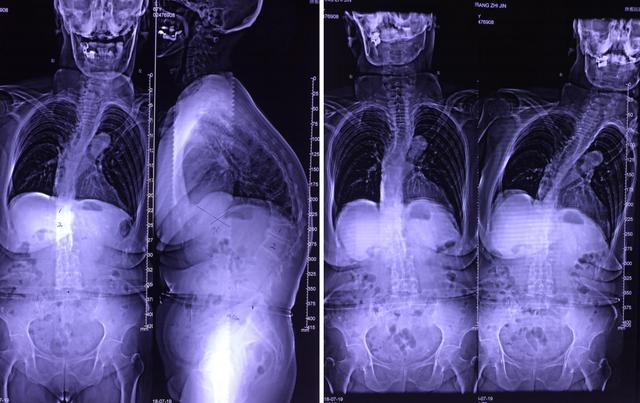

术前(左)术后(右)

术后3个月后复查:术后影像学检查:术前(左)术后(右)术前(左)术后(右)